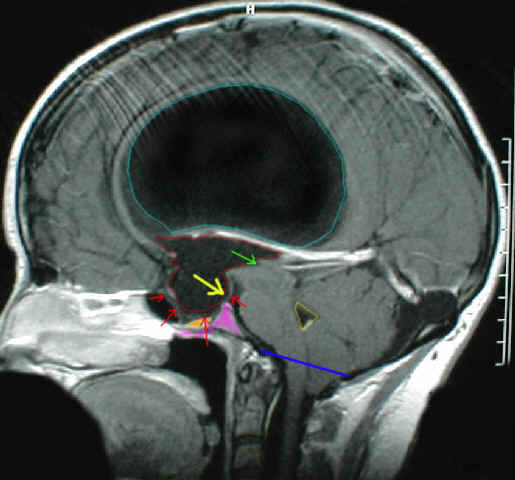

Die Abbildung zeigt einen Okklusionshydrocephalus, der mehrere Ursachen hat: einerseits besteht eine Aquäduktstenose. Der Eingang in den Aquädukt ist mit einem grünen Pfeil markiert. In diesem Kernspin ist der Aquädukt aber nicht sichtbar; entweder ist er völlig verschlossen oder so eng, dass er im MRI nicht einsehbar ist. Darüberhinaus hat der Patient eine so genannte Chiari Malformation; damit ist der Abfluß des Liquors aus dem (gelb umrandeten) IV. Ventrikel in die äußeren Liquorräume nicht möglich. ... soweit eigentlich ein idealer Kasus für eine endoskopische Therapie. ABER: Der Boden (rote Pfeile) des III. Ventrikels (mit roter Linie umrandet) ist so weit nach unten vorgewölbt in die so genannte Sella turcica (lila markiert), die knöcherne Lager der Hirnanhangdrüse (orange markiert) ist, dass die anatomischen Voraussetzungen für eine endoskopische Operation sehr kritisch sind. Dort, wo der gelbe Pfeil ist müßte man eigentlich das Loch in den Boden des III. Ventrikels machen. Es liegt jedoch direkt auf der Unterseite des Bodens des III. Ventrikels ein großes Blutgefäß, das auch nicht ausweichen könnte, da es sich direkt an den Hirnstamm anlehnt. Bei diesem Patienten ist demzufolge eine endoskopische Operation wegen der Begebenheiten am Boden des III. Ventrikels nicht oder nur mit erheblichen Risiken möglich. Die sichere Variante ist es hier einen Shunt als Therapie der Wahl anzusehen.